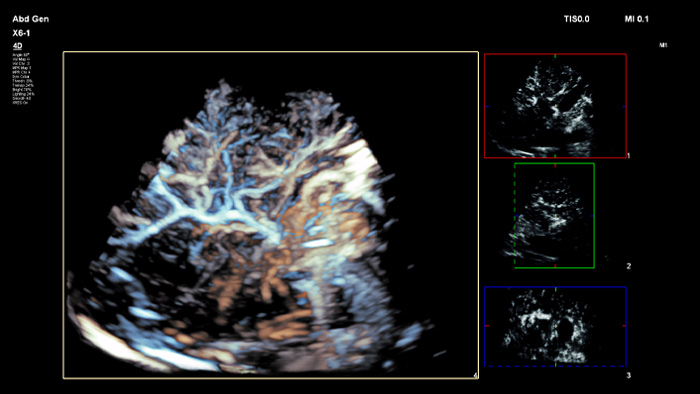

Prendi decisioni sicure anche in casi diagnostici complessi grazie alla fusione delle immagini e alla navigazione dell'ago di Philips. Il flusso di lavoro semplificato consente ai medici di ottenere una fusione rapida ed efficace di immagini TC/RM/PET con ecografia dal vivo, mentre la navigazione dell'ago aiuta a guidare la biopsia di lesioni di piccole dimensioni e di difficile accesso2.

Utilizzando il contorno del tumore, gli utenti possono pianificare e trattare le lesioni con uno strumento semiautomatico che aiuta a delineare un contorno 3D attorno a una struttura di interesse, migliorando potenzialmente la guida della procedura nei casi difficili in cui la lesione potrebbe non essere facilmente visualizzata.